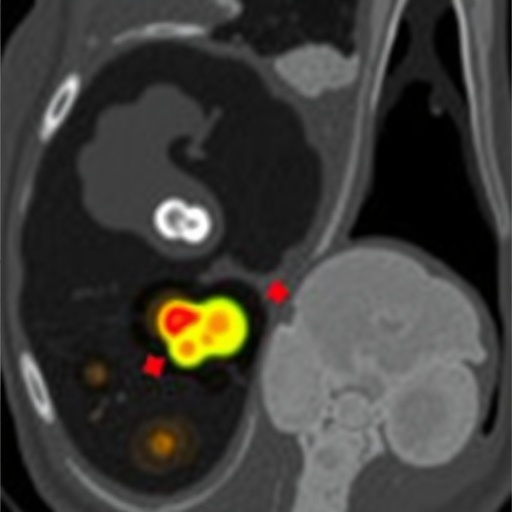

The diagnosis of RMS often involves advanced imaging modalities and a comprehensive histopathological evaluation to confirm the presence of malignant rhabdomyoblasts. For the patient in this report, the detection of metastasis was a daunting moment, leading to the reevaluation of their treatment protocol. Bone marrow metastasis has significant prognostic implications, suggesting a more aggressive tumor biology and necessitating a more intensive therapeutic strategy.

Traditionally, bone marrow involvement in pediatric cancers has been observed more frequently in hematological malignancies. The presence of solid tumor metastasis in the bone marrow often suggests a later-stage disease and often corresponds to poorer outcome measures. This particular case illustrates that clinicians and researchers need to maintain vigilance regarding atypical presentations of RMS, as early detection can significantly influence survivorship outcomes.